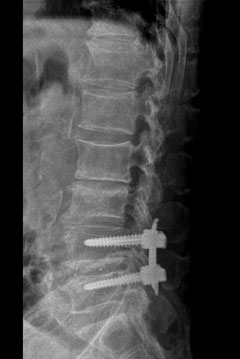

척추관협착증 환자의 등뼈에 경피적유합술을 통해 척추 고정용 나사를 심은 모습. / 사진제공 제일정형외과병원

척추관협착증은 척추디스크가 닳거나 척추 관절의 노화로 척추뼈를 제대로 지지하지 못하고 흔들리는 '척추분리증'이나 분리된 척추뼈가 앞으로 쏠리면서 신경을 자극해 통증을 일으키는 '전방전위증'을 동반하는 경우가 많다. 이런 경우 척추가 흔들리지 않도록 척추뼈를 나사못으로 고정하는 척추유합술을 해야 한다. 기존 척추유합술은 전신마취를 하고 척추가 있는 등의 중앙부를 10cm 이상 절개한 뒤 근육과 신경 조직을 뼈에서 분리하기 때문에 수술부위가 상당히 크고 회복이 오래 걸린다. 그러나 요즘은 척추뼈를 고정할 부위에 나사만 들어갈 정도로 약 1cm 정도만 절개하고 피부로 나사를 넣고 투시 엑스레이와 디스플레이를 보면서 척추뼈를 고정하는 경피적유합술을 많이 시술한다.